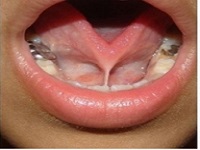

They are essential immunity organs (two bulges in the throat) especially in childhood. But many a times they themselves become a site of infection leading to acute tonsillitis which may become chronic. Majority of the times, the tonsil problems can be dealt with basic medicines by oral or IV route. But if it becomes a Chronic problem then it might need surgical removal i.e. Tonsillectomy.

Tonsillectomy is a safe procedure and yields great relief to the patients. Best ENT Surgeon will wisely decide whether you need or don’t need Tonsillectomy. If untreated it may lead to: